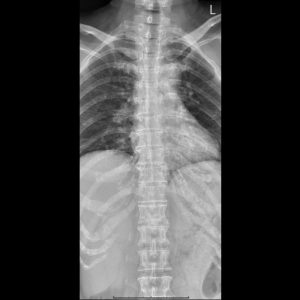

T-spine A-P view

T-L spine AP view